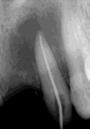

Las Figuras 1-3 muestran las imágenes de la cavidad bucal de la paciente. Se puede observar el deterioro generalizado de la salud bucodental, destacando la higiene dental deficiente, gingivitis, restauraciones dentales desajustadas, exposiciones radiculares, anodoncias parciales y caries radiogénica.

Las Figuras 4-13 son imágenes radiográficas de los dientes de la paciente que presen tan múltiples lesiones periapicales como consecuencia de las necrosis pulpares originadas por la radioterapia. Se realizaron los

tratamientos y retratamientos endodónticos necesarios para preservar los dientes en boca, evitando las exodoncias y por lo tanto minimizando el riesgo de generar osteorradionecrosis.